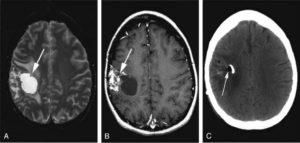

Кроме того, данные способы обследования позволяют сделать дифференциальную диагностику промежуточного состояния между доброкачественной кистой и злокачественной опухолью. После внутривенного введения специального контрастного вещества его продукт накапливается в опухолевых тканях, а киста при этом не становится контрастной.

- арахноидальная киста. Распространённость арахноидальных кист по данным нейровизуализационных методов (КТ/МРТ) около 4%. Это полость, образованная удвоением паутинной оболочки, которая со временем заполняется ликвором. Иногда кисты развиваются в результате спаечных процессов между арахноидальной и мягкой мозговыми оболочками. Такие кисты могут сообщаться с субарахноидальным пространством. Излюбленной локализацией кист является боковая (сильвиева) щель мозга – 45 — 50%, мостомозжечковый угол – 10%, четверохолмие – 10%. Даже при огромных размерах эти кисты зачастую бессимптомны. Опасными являются образования с клапанным механизмом. То есть подобная киста наполняется ликвором, но обратного оттока нет, поэтому происходит её быстрый рост и сдавление окружающих структур мозга. Самая распространённая киста среди взрослого населения;

- инсульты головного мозга. Если киста возникает на месте инфаркта мозга, то её стенки и содержимое зачастую прозрачные, если на месте геморрагического инсульта, то в результате распада гемоглобина стенки окрашиваются в рыжий, коричневый цвет;

- КТ и МРТ головного мозга — на данный момент самые достоверные методы обследования, позволяющие не только обнаружить кисту и определить её точную локализацию, но и узнать её гистологическую структуру. Для выявления такой патологии, как киста головного мозга, чаще используют МРТ, так как этот метод более чувствителен к мягким тканям и не даёт «слепых зон» в отличие от КТ. Имеется в виду, что при использовании КТ плохо визуализируются структуры мозга, расположенные в задней черепной ямке. Если всё-таки нет возможности провести МР исследование, то выполняют КТ с внутривенным усилением, то есть вводится контрастное вещество;

- церебральная ангиография — метод, основанный на введении контрастного вещества в артериальное русло пациента с последующим проведением рентгенографии. Применяется для дифференциальной диагностики кисты мозга, опухоли и аневризмы сосудов головного мозга. Также позволяет выявить дислокацию сосудов в области кисты;